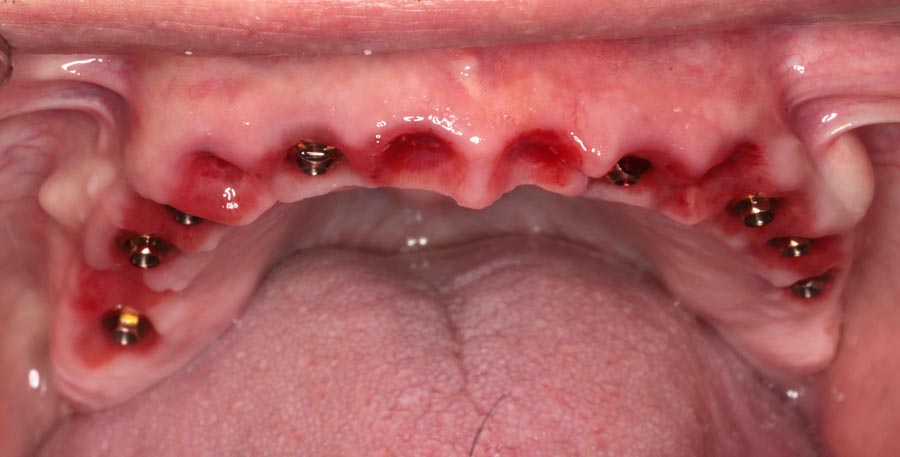

Three months later the patient returns for a series of appointments to fabricate his final prostheses. This is when we note that his homecare is slipping. Notice the redness at the gums that wasn’t seen previously. He was alerted to the issue and educated on how to improve.